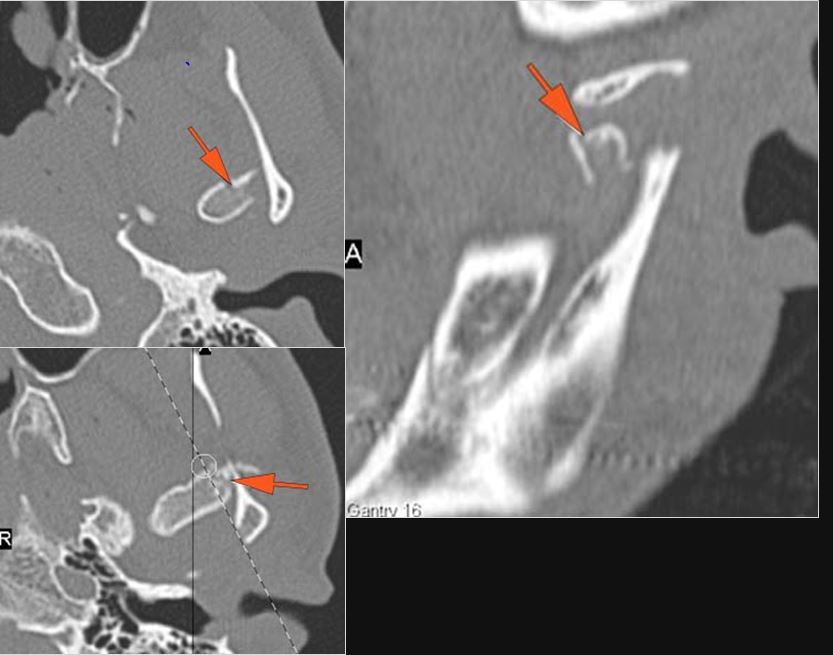

Nasolacrimal Canal and Sac

There is bony injury to the nasolacrimal canal.

The nasolacrimal sac appears to be intact.